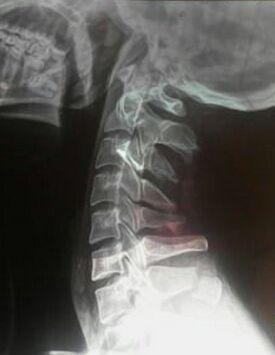

常见于铲土工和矿工,故又称为“铲土工”骨折。棘突是椎体上与肌肉附着点的部分(图1)。做一个简单的棘突定位,如第7颈椎棘突是颈椎棘突最隆起的一个。当低头时,在项部下方正中线上最突出的一个,能随摇头而左右摇动,而其下方的第1

常见的颈椎棘突骨折来说,一般由于巨大的暴力直接作用于颈椎部位引起棘突骨折,但常因暴力过大而伴有其他后方结构的损伤,患者一般受伤较为严重,骨折累及多个棘突。

通常高处坠落以及交通事故时,颈椎过屈牵拉暴力导致附着在棘突的肌肉如斜方肌、大小菱形肌等不协调收缩牵拉,造成后方韧带复合体的撕裂。

疲劳性骨折:此类骨折通常称作Clay shoveler 骨折,即“铲土者骨折”,是指附着在棘突上的肌肉强力收缩引起的撕脱剥离性骨折,目前主要 泛指发生在下颈椎、上胸椎棘突的撕脱骨折。这是因为